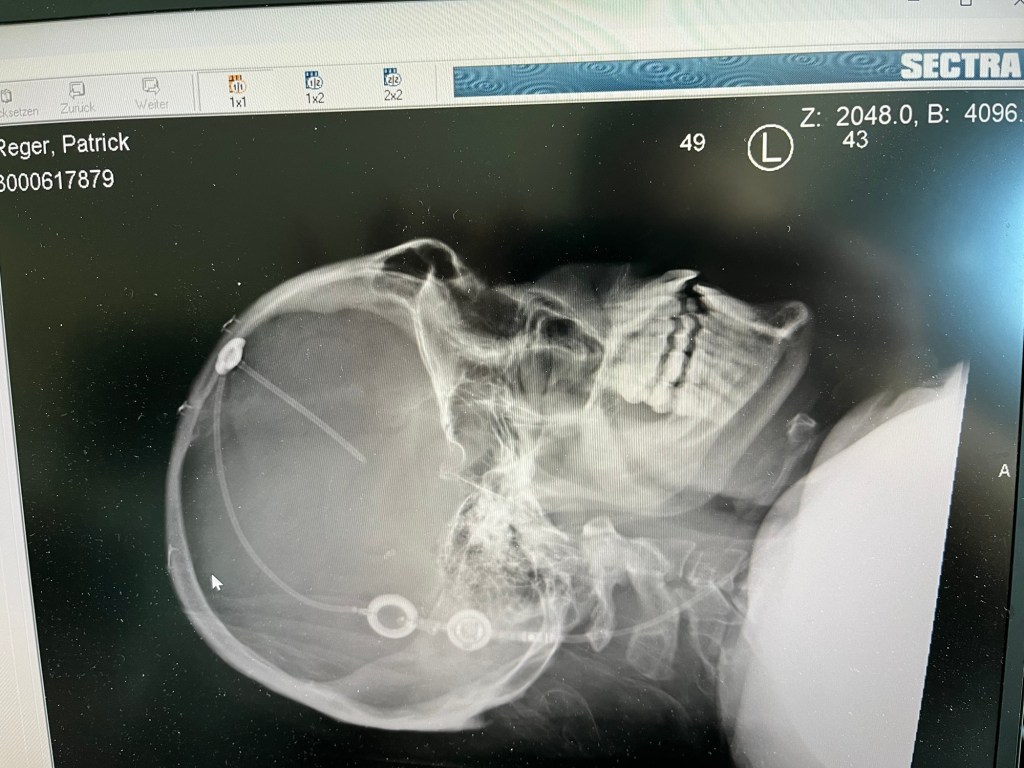

Hier sieht man ganz gut wo/wie der Shunt im Hirn 🧠 sitzt

Krass, sehe ich auch zum ersten Mal sowas